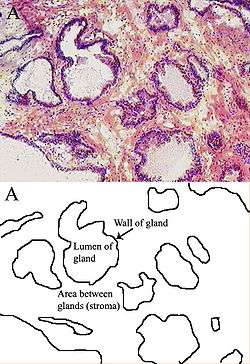

Histology

- Glandular cells

- Myoepithelial cells

- Subepithelial interstitial cells[17]

Prostate Microscopic glands of the prostate

Microscopic glands of the prostate Male Anatomy